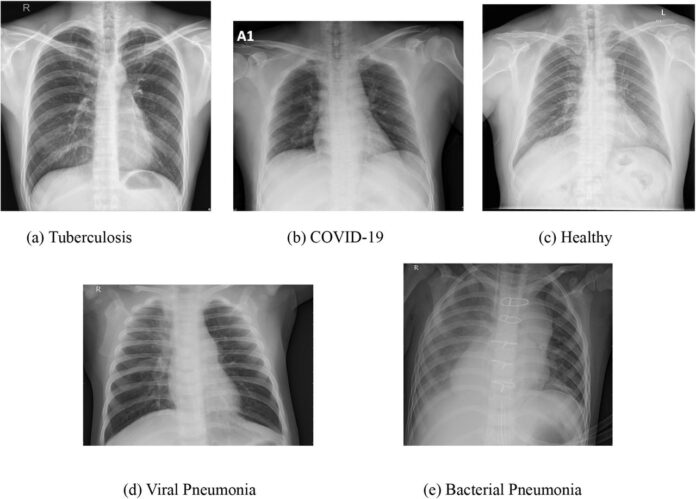

Bakteryjne zmiany są najczęściej jednostronne i ostre, z wyraźnym air bronchogramem – widocznymi oskrzelami wypełnionymi powietrzem na tle zacienionego miąższu. Wirusowe zapalenie płuc, np. wywołane grypą lub RSV, prezentuje się inaczej: dominują międzypłatowe nacieki o charakterze międzywrzodowym, rozproszone obustronnie. Te ziarniste lub siateczkowate zmiany zajmują oba płuca w 60-90% przypadków, bez homogennej konsolidacji.

Wirusowe postacie zapalenia płuc na zdjęciach rentgenowskich klatki piersiowej często przypominają obrzęk płucny, z perihilarnymi smugami i zagęszczeniami w dolnych polach. Bakteryjne zapalenie płuc wykazuje z kolei szybką ewolucję – konsolidacja może ustąpić po 48-72 godzinach antybiotykoterapii, co potwierdza RTG kontrolne. Frazy takie jak charakterystyczne cechy bakteryjnego zapalenia płuc w rentgenie pomagają radiologom w szybkim różnicowaniu.

Obraz radiologiczny wirusowego zapalenia płuc bywa subtelny, z hiperaeracją płuc i brakiem płynu w jamie opłucnowej, co odróżnia je od bakteryjnych ropni. W badaniach z lat 2010-2020, np. te publikowane w Radiology, aż 75% wirusowych przypadków wymagało potwierdzenia tomografią komputerową z powodu niejednoznaczności RTG. Te różnice między bakteryjnym a wirusowym zapaleniem płuc w obrazie rentgenowskim wpływają na dobór terapii.